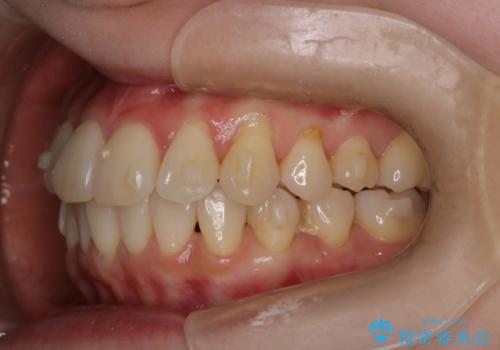

- インビザラインで非抜歯治療を行いました。IPRと拡大をし、叢生、咬合をきれいにしました。

主訴であったかみ合わせを正しい位置に動かし、バランスよくかめるようになりました。矯正治療終了後にメタルインレーをセラミックインレーに替えました。